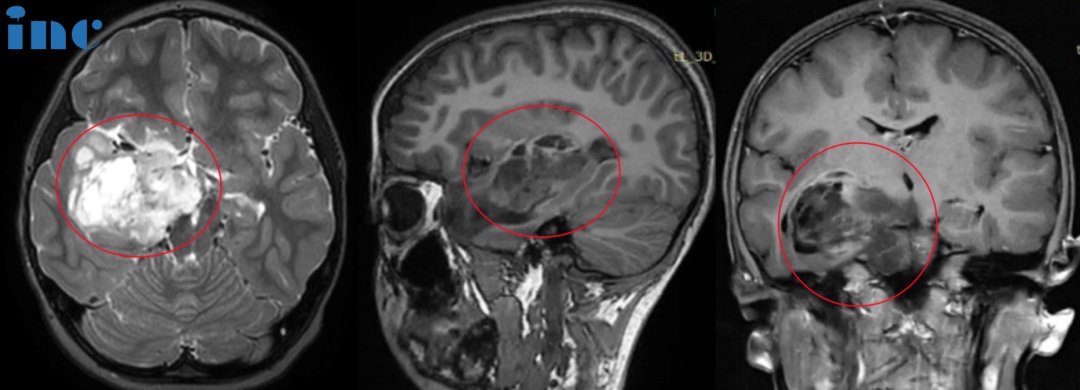

▼可可术前术后影像对比

可可术后病理结果为WHO1级胶质瘤,这代表着预后很好,可以长期生存,甚至可以和正常孩子一样生活。手术后的可可恢复了本来的开心、健康和活力,将重拾自己的舞蹈梦想。总结自家的经历,可可妈妈希望和病友交流以下几点:

巴教授凭着其多年的成功手术经验明确表示:可可的核磁显示很可能符合低级别胶质瘤。在 MRI 上没有恶性肿瘤的迹象。预期切除率将超过 90%,这取决于术中的情况。我过去曾成功地为患有类似肿瘤的儿童做过手术,切除率也很高。可可妈妈终于看到了希望,这是黑暗中的一线生机,需抓住!

在苏州大学附属儿童医院,手术顺利。这场手术由巴教授主刀,国内神经外科医生团队配合。在术中导航、术中神经电生理监测的护航下;巴教授通过不同的体位和高超的手术技术,在不损伤神经功能的情况下,较大水平切除肿瘤,无新发功能缺损。